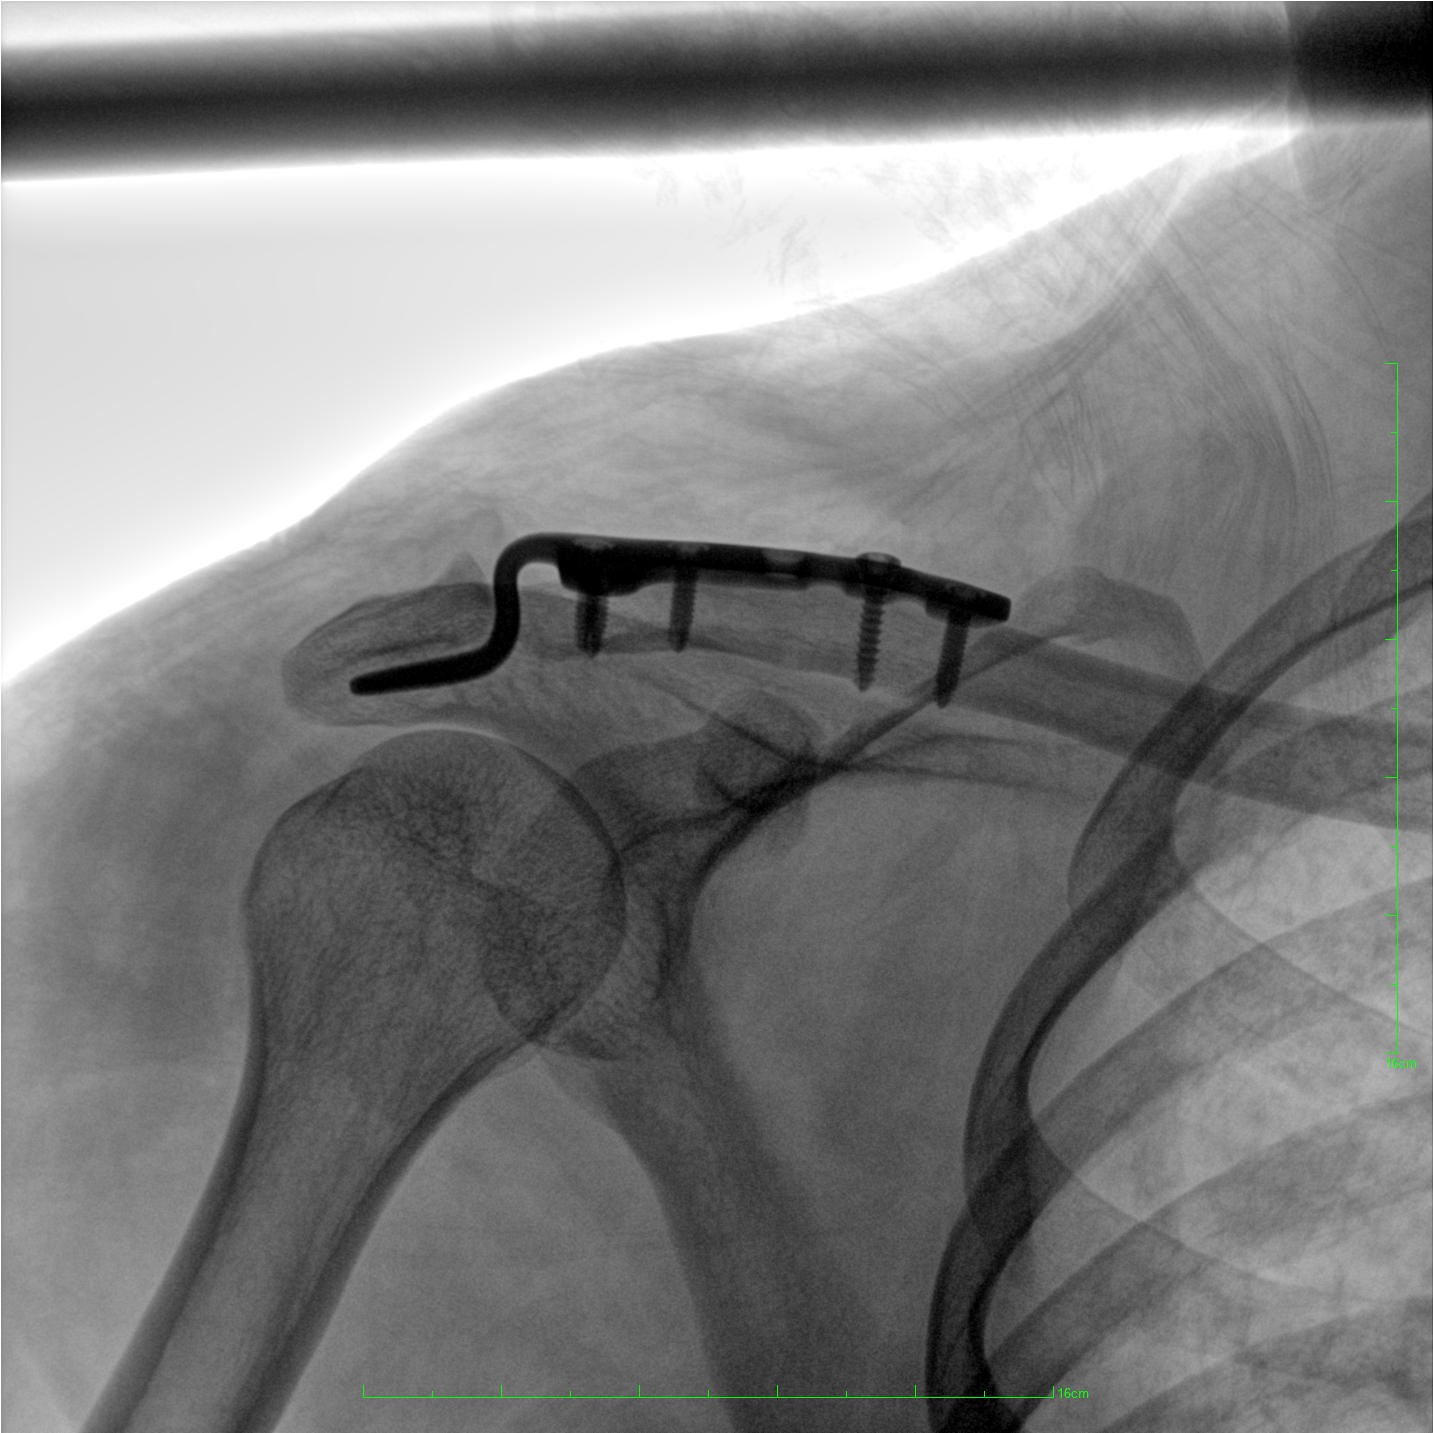

術中三維成像和橫斷面圖像提供多角度的手術診斷信息,輔助醫生進行術中評估判斷,諸如骨折復位情況和內植入螺釘的尺寸和位置,輔助手術更好地完成。

提供更大的術中三維成像視野,采集更多圖像信息,可一次拍全全段頸椎、全段腰椎、七節胸椎、雙側骶髂關節、股骨頭及單側盆骨。

平板垂直升降運動 便于術中微調平板與拍攝主體的距離,更加貼近病灶體,成像范圍更大,圖像更清晰。